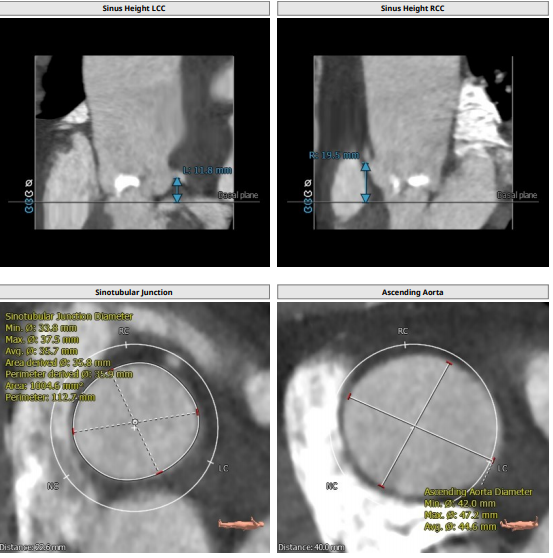

此例患者大横位Type0型二叶瓣,瓣环径23.1,LVOT22.6,Stj35.9,左冠高度11.8,右冠19.5,术前根据总体结构使用20MM球囊预扩,抓捕器辅助瓣膜通过横位结构跨瓣,术前预装VenusA23号瓣膜。

根部解剖: